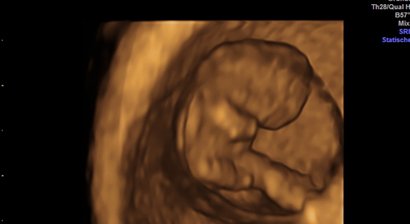

2D, 3D, 4D Ultraschall

Die Ultraschalluntersuchung ist heute von einer kompetenten Frauenarzt-Praxis nicht mehr wegzudenken. Wir verfügen seit 2015 über ein extrem hochwertiges Ultraschallgerät, das neben einer sehr guten Bildauflösung Techniken wie 3D Ultraschall, 4D Ultraschall und verbesserten Doppl...